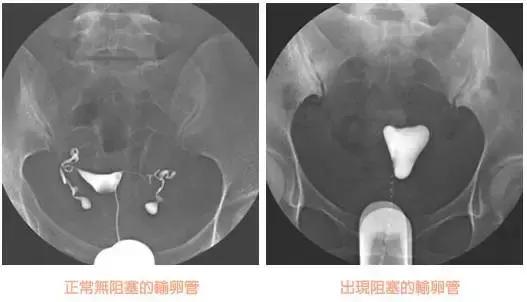

怎么看懂造影片,啥也不说,上图